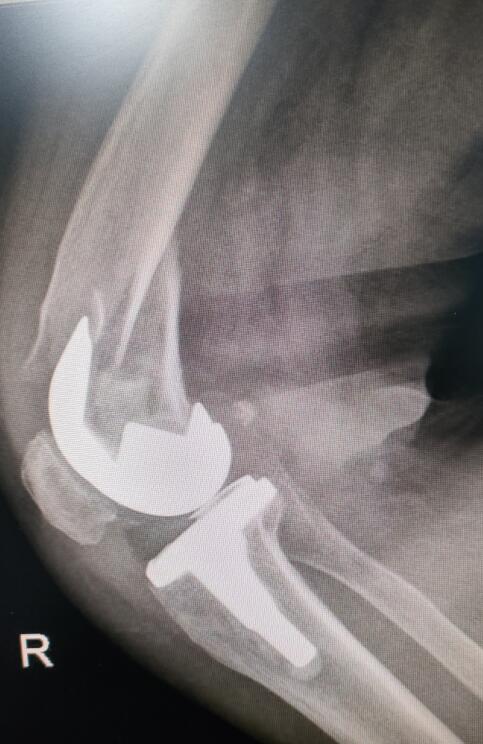

手術(shù)前照片

手術(shù)后照片

原來(lái),5年前吳阿姨因?yàn)閲?yán)重的膝關(guān)節(jié)炎不能行走,在中醫(yī)院行雙膝置換,前不久因摔傷導(dǎo)致“人工關(guān)節(jié)”假體周?chē)l(fā)生骨折,只能臥床的吳阿姨再次來(lái)到瀘州市中醫(yī)醫(yī)院接受了人工關(guān)節(jié)“翻修”和骨折內(nèi)固定手術(shù)。術(shù)后,又能“站起來(lái)”的吳阿姨順利出院,回家休養(yǎng)。“醫(yī)院兩次讓我站了起來(lái)。5年前第一次在這里換了‘關(guān)節(jié)’,現(xiàn)在又是骨折,太多的感謝無(wú)法表達(dá),所以想送點(diǎn)小禮物表達(dá)心意?!?/span>

骨折部位在假體周?chē)?,患者還患有嚴(yán)重的內(nèi)風(fēng)濕、骨質(zhì)疏松、高血壓……能否耐受這臺(tái)復(fù)雜而高難度的關(guān)節(jié)翻修與骨折手術(shù)?這對(duì)醫(yī)院骨傷三科醫(yī)護(hù)團(tuán)隊(duì)來(lái)說(shuō),是一個(gè)不小的挑戰(zhàn)。

“關(guān)節(jié)假體需要進(jìn)行‘翻修’固定,要保證骨折部位修復(fù)后假體的穩(wěn)定性,還要考慮患者年齡大,曾接受過(guò)多次手術(shù),患有多種基礎(chǔ)疾病,手術(shù)技術(shù)難度高,對(duì)醫(yī)生和患者都是一次挑戰(zhàn)?!弊鳛槭中g(shù)團(tuán)隊(duì)成員和吳阿姨主管醫(yī)生的王旌晶覺(jué)得一定要對(duì)得起患者及家屬這份沉甸甸的信任。